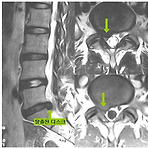

추간판 탈출증 운동 방법을 아라보자 추간판 탈출증(디스크)는 추간원판의 전위에 의해 섬유륜의 파열, 수핵의 일부 또는 전부가 탈출되어 척수의 경막이나 신경근을 압박하여 신경증상을 유발하는 병입니다. 추간판탈출증 운동방법 1. 부분 윗몸 일으키기 운동 2. 네발 기기 자세에서 팔다리 올리기 3. 대둔근 스트레칭 4. 엉덩이, 골반 들어올리기 5. 허리 비틀기 6. 양다리 굽혔다 펴기 운동 추간판탈출증의 증상 경추 추간판 탈출증(목 디스크) 요추 추간판 탈출증(허리 디스크) -경추부 통증과 강직이 나타납니다. -진행하게 되면 목, 어깨, 관절, 팔등에 통증과 쇠약, 손가락의 감각이상이 발생합니다. -허리 통증, 둥부, 하퇴, 하지부위의 해당 신경근 분포에 따라 방사통(좌골신경통)이 발생하고 하지의 감각이상,..